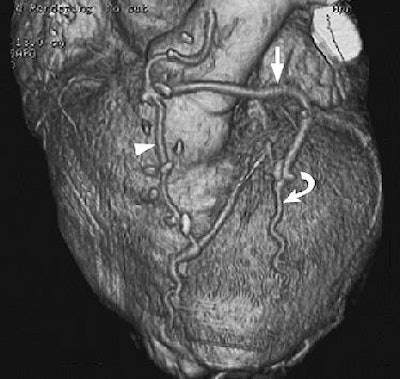

| Minimization of stepladder artifacts with maintenance of an optimal heart rate and selection of an optimal reconstruction window. Volume-rendered images reconstructed from data acquired at 40% (a, above) and 70% (b, below) of the R-R interval, with a heart rate of 55 beats per minute, show a stepladder artifact, which is less pronounced in (b). Note also the improved depiction in (b) of patency both in the in situ graft of the left internal mammary artery to the distal left anterior descending artery (arrowhead) and in the Y-graft (straight arrow) of a radial artery from the left internal mammary artery to the diagonal artery (curved arrow). Figure 5a, b, Choi HS, Choi BW, Choe KP, et al. Pitfalls, artifacts, and remedies in multi-detector row CT coronary angiography. RadioGraphics 2004; 23:787-800. |